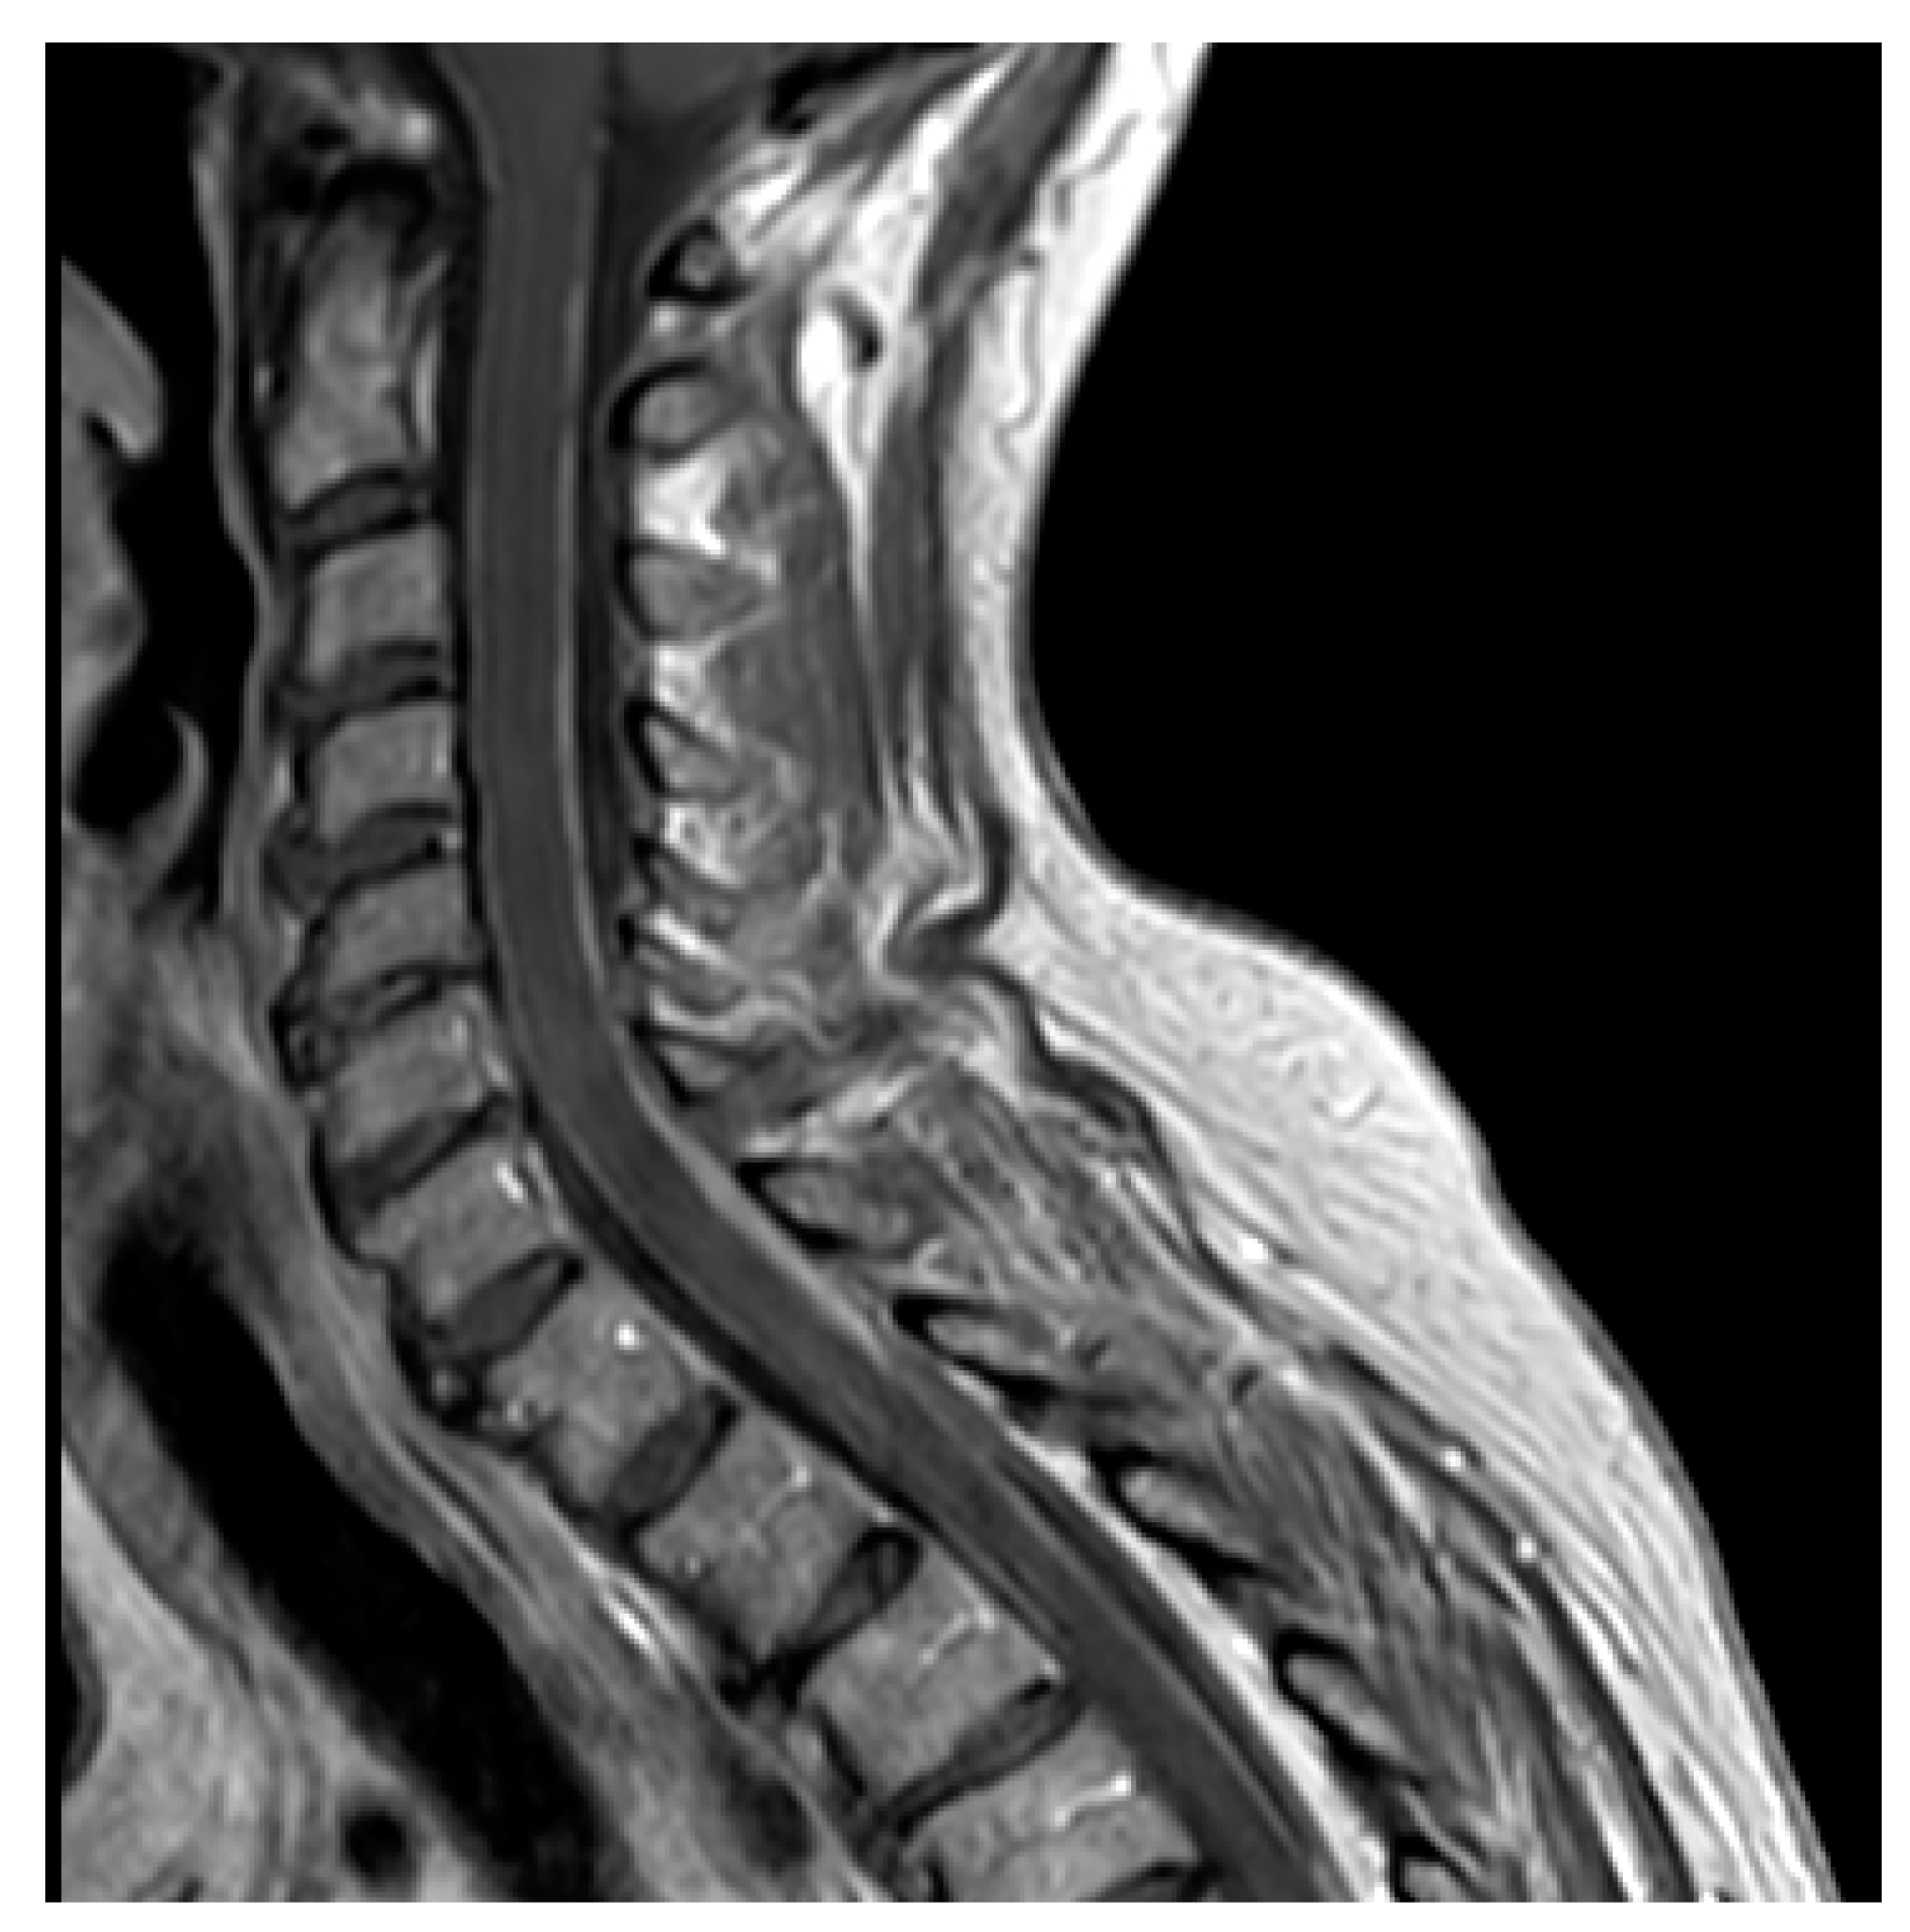

4.2. Neuroimaging Assessment

4.3. CSF Cytology and Liquid Biopsy